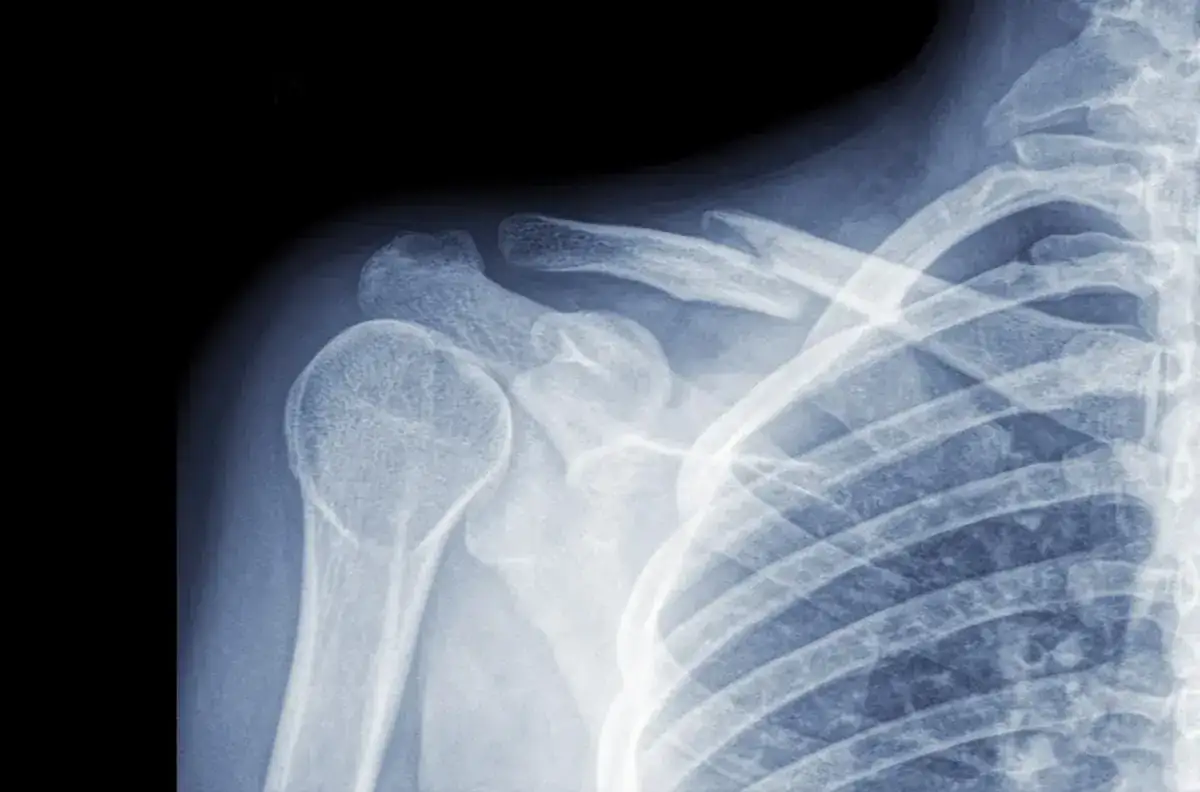

Kluczowym elementem diagnozy jest badanie obrazowe. RTG to podstawowe narzędzie, które pozwala potwierdzić złamanie i określić jego rodzaj. W niektórych przypadkach mogą być potrzebne dodatkowe badania, takie jak USG czy tomografia komputerowa.

RTG to podstawowe badanie w diagnostyce złamanego obojczyka u dziecka. Zdjęcie rentgenowskie pozwala dokładnie ocenić rodzaj złamania, jego lokalizację i ewentualne przemieszczenie odłamków kostnych. To kluczowe informacje dla planowania leczenia.

W niektórych przypadkach lekarz może zalecić USG, które jest szczególnie przydatne u małych dzieci. Tomografia komputerowa jest rzadko stosowana, głównie przy skomplikowanych złamaniach lub podejrzeniu dodatkowych urazów.